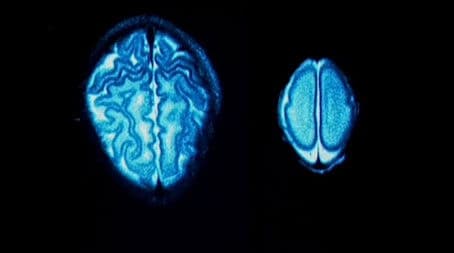

The topic of this episode is intelligence. Is it possible for parents to increase or decrease their child's intelligence, or is intelligence simply fixed in our genes? The baby's brain increases by 3 times in the first year, so factors such as nutrition, whether a baby is premature or not, and environmental stimulation are critical.